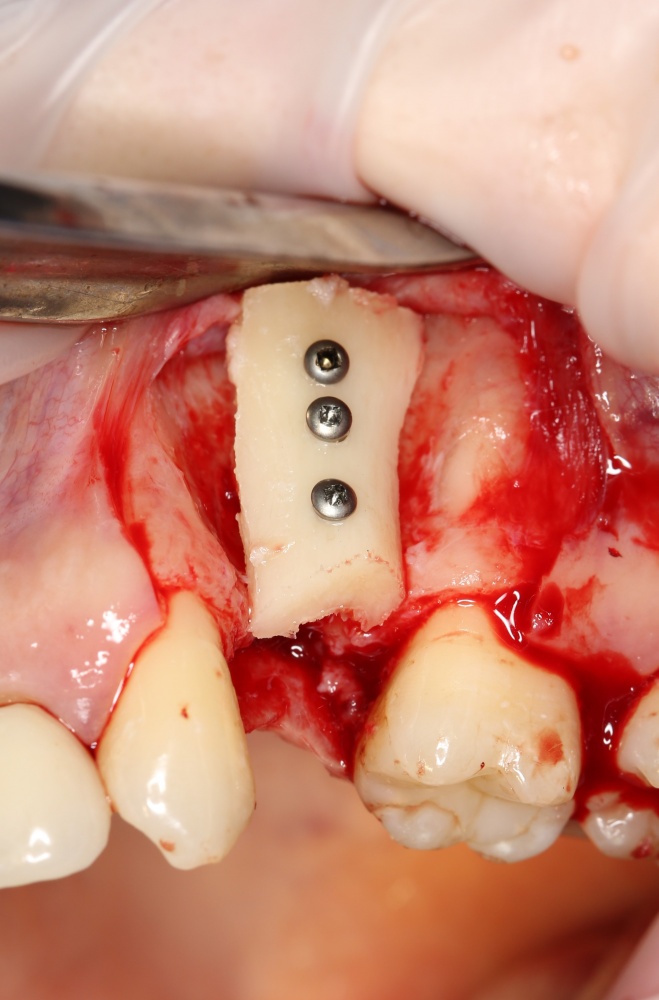

Вторая особенность — мы не адаптируем и не обрабатываем костный блок invitro, а фиксируем его так, как есть:

после чего обрабатываем — доводим до окончательной формы альвеолярного гребня: